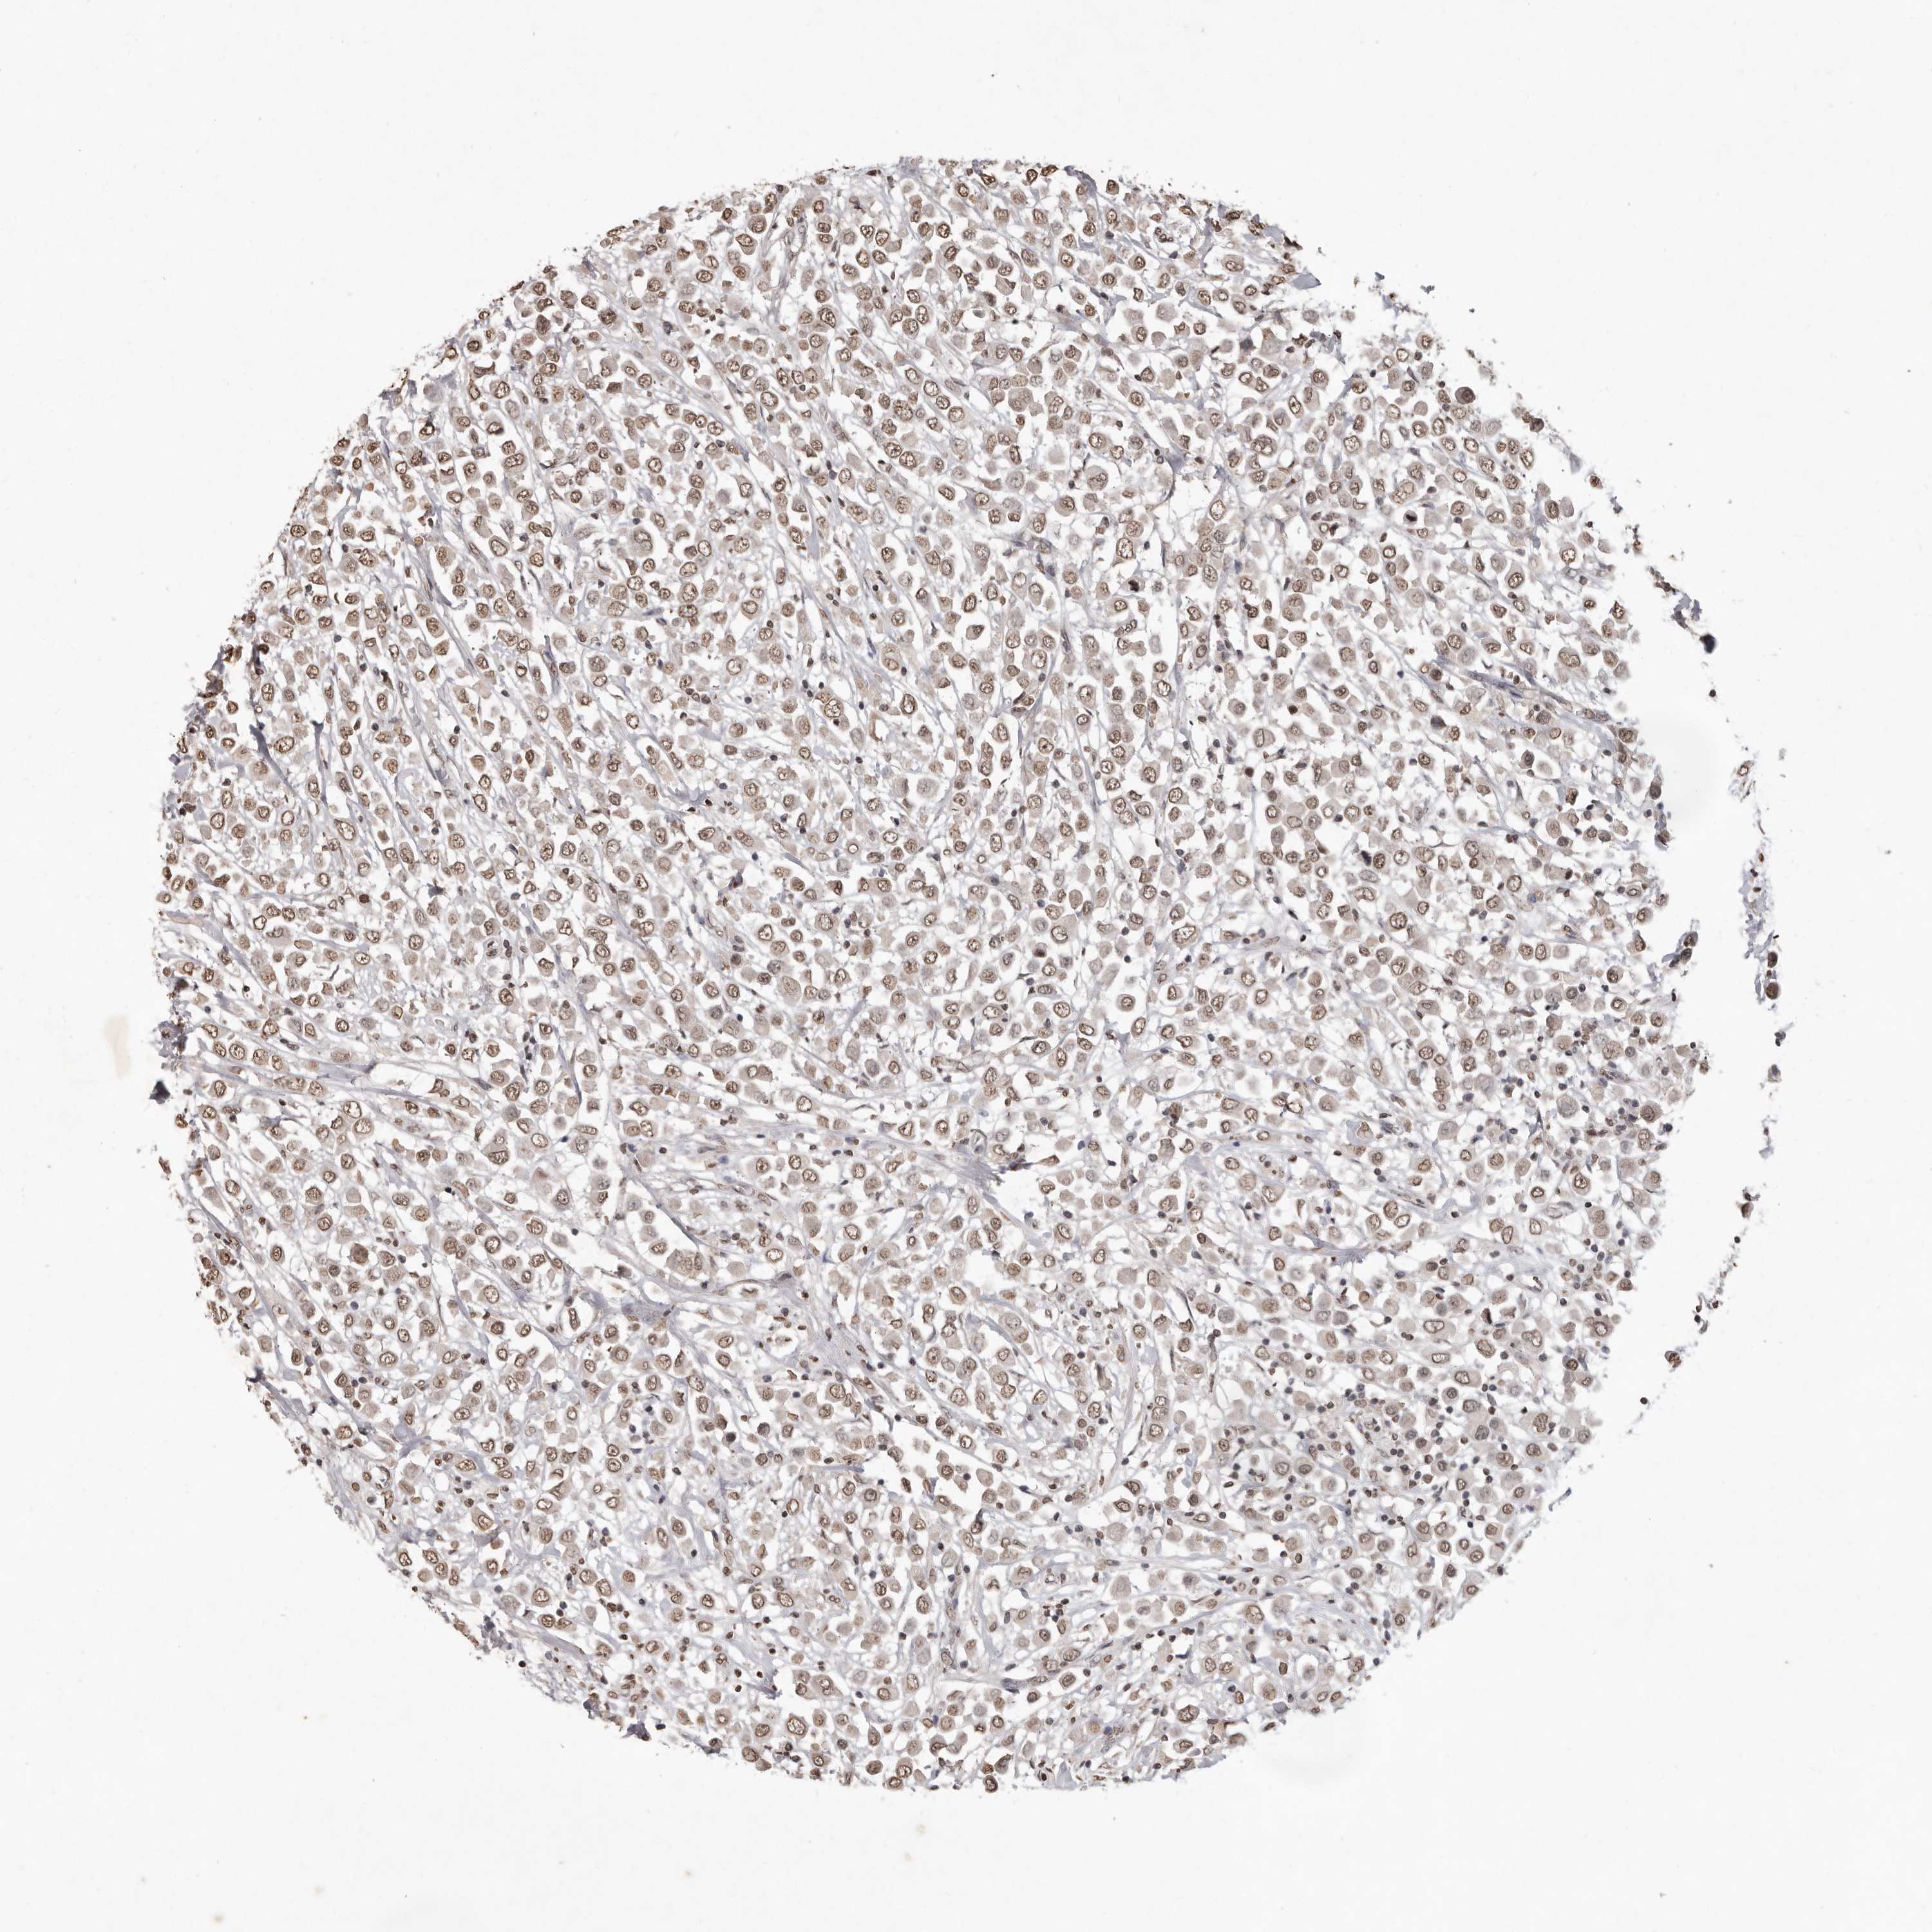

BRCA TCGA BRCA VALIDATION PROTEIN EXPRESSION